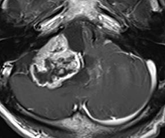

以下の画像に呈示するような脳幹や小脳を圧迫する大きい腫瘍に対しては、開頭手術が優先されます。手術中に神経刺激装置・聴性脳幹反応など電気生理学的モニタリングを併用し、1つ1つの手術操作によって神経機能を損傷していないか随時チェックしながら手術を行っており、術後後遺症の予防に努めています。